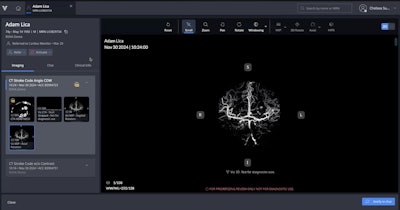

Viz 3D CTA AI software, Viz.ai

Introduced in April, our other Best New Radiology Software contender is a neurovascular imaging application that automatically converts CT angiography (CTA) scans into high-resolution AI-enhanced 3D images.

Viz 3D CTA automatically converts CT angiography scans into high-resolution AI-enhanced 3D images.Viz.ai

Viz 3D CTA automatically converts CT angiography scans into high-resolution AI-enhanced 3D images.Viz.ai

The company said that Viz 3D CTA addresses challenges in neurovascular imaging, including delays due to manual 3D renderings, limited spatial context in PACS, and difficulty viewing smaller or more distal vessel abnormalities. The software also features automated postprocessing, skull-stripped views, and interactive tools such as sagittal and axial rotation, according to Viz.ai.

“Fully integrated into the Viz.ai platform, this capability enables care teams to interact with complex neurovascular anatomy in real-time — automatically removing bone and venous structures to enhance clarity and support time savings in stroke and aneurysm workflows,” said Chelsea Summerour, associate director for product management.